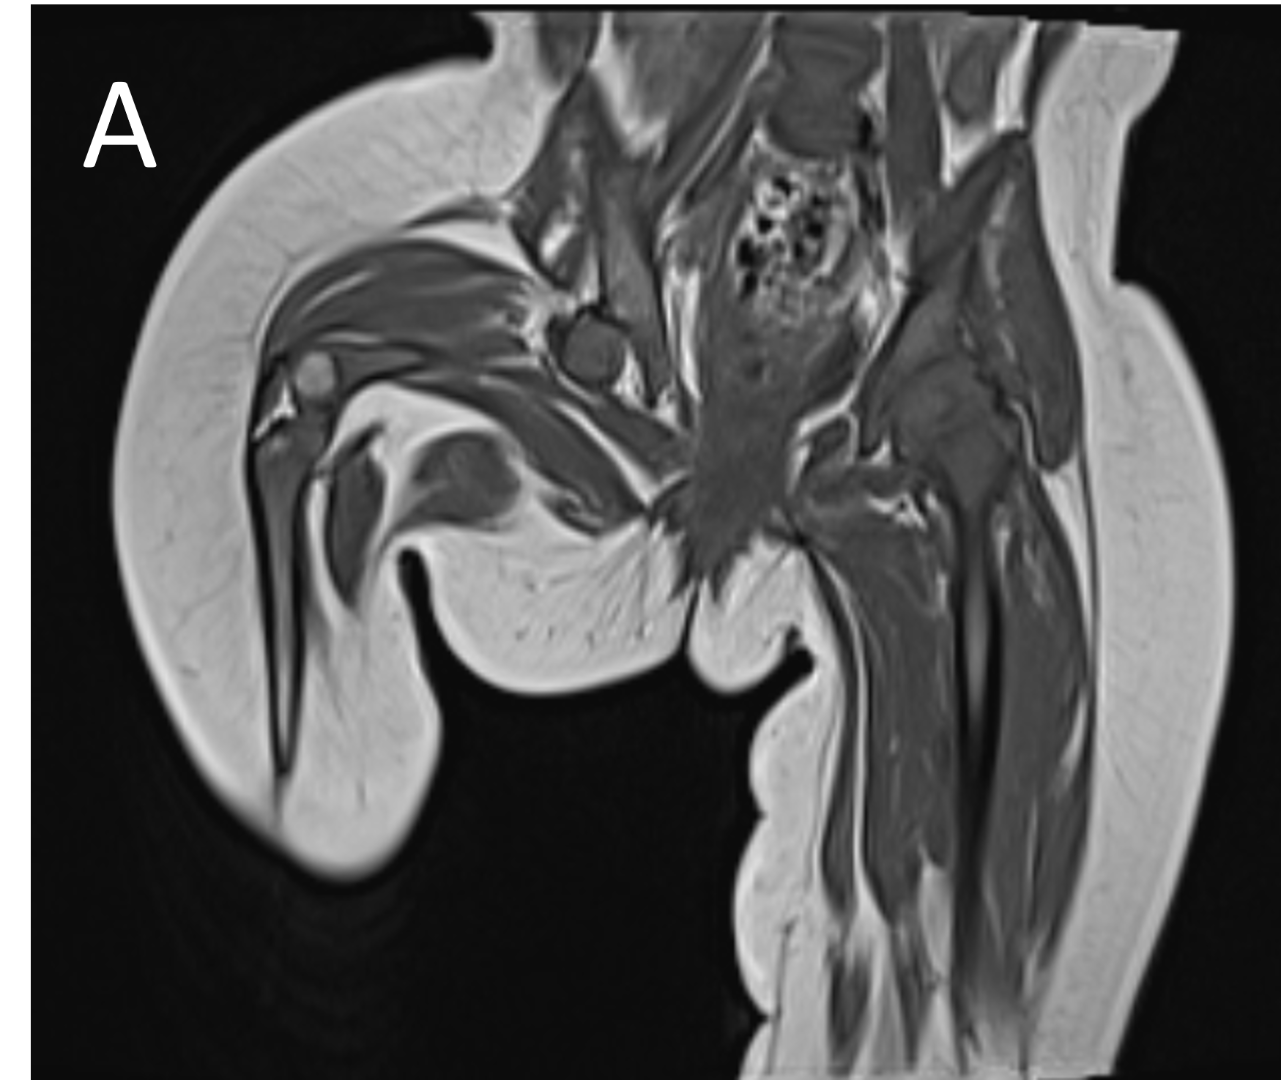

- A.FINDINGS – MR BILATERAL HIPS

- B.FINDINGS – MR BILATERAL HIPS

- A.LEGENDS – MR BILATERAL HIPS :Right femur is shortened, with a coxa vara deformity. Femoral shaft measures 7.2 cm in length. The acetabulum is moderately dysplastic and anteriorly rotated, But contains the femoral head. The femoral head and neck appear hypoplastic and posteriorly and externally rotated.

- B.LEGENDS – MR BILATERAL HIPS : Generalised atrophy of muscles of thigh and gluteal region on the right compared to the left.